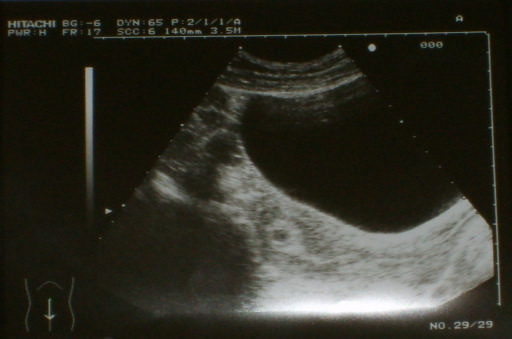

Ma megyek a dokimhoz, ma van Uh. Remélem ott van a pici és dobog a kis szivecskéje, és csak megijesztett. Nem élem bele magam mert ha nem így van akkor tönkre megyek!!!!!